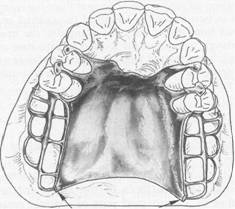

Fig. 5-36 Complete coverage palatal major connec­tor. Posterior border terminates at junction of hard and soft palates. Anterior portion, in the form of palatal linguoplate, is supported by positive lingual rest seats on canines. Location of finishing lines is most important in this type of major connector. Anteroposteriorly, they should be parallel to a line along the center of the ridge crest and located just lingual to an imaginary line contacting lingual surfaces of missing natural teeth. Alteration of natural palatal contour should be anticipated with its atten­dant detrimental effect on speech if these contours are not followed.